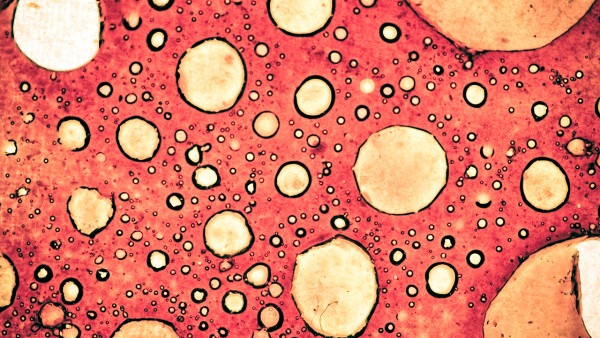

研究人员指出,真菌遍布植物界,植物和真菌经常协同工作,其中一些真菌会杀死竞争对手或阻止昆虫吃掉植物。他们假设,如果这些植物内生真菌能够通过杀死入侵的真菌来帮助植物抵御感染,那么这些分子或许能保护人类和动物免受真菌病原体的侵害。

在研究中,希彻韦兹团队开发出一种独特的方法来测试植物的抗真菌特性。他们使用快速激光内生植物捕捉器(FLEET),在无菌环境中生成样本,并大幅增加可获取的样本数量。结果显示,传统方法每分钟可处理大约4—6个样本,但FLEET系统能在10分钟内无菌生成500—600个样本,这使研究人员能够快速筛选更多样本,发现潜在药物,并最终发现了新分子persephacin。